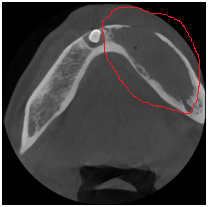

◆埋伏牙

◆牙瘤

◆由囊肿引起的骨质破坏